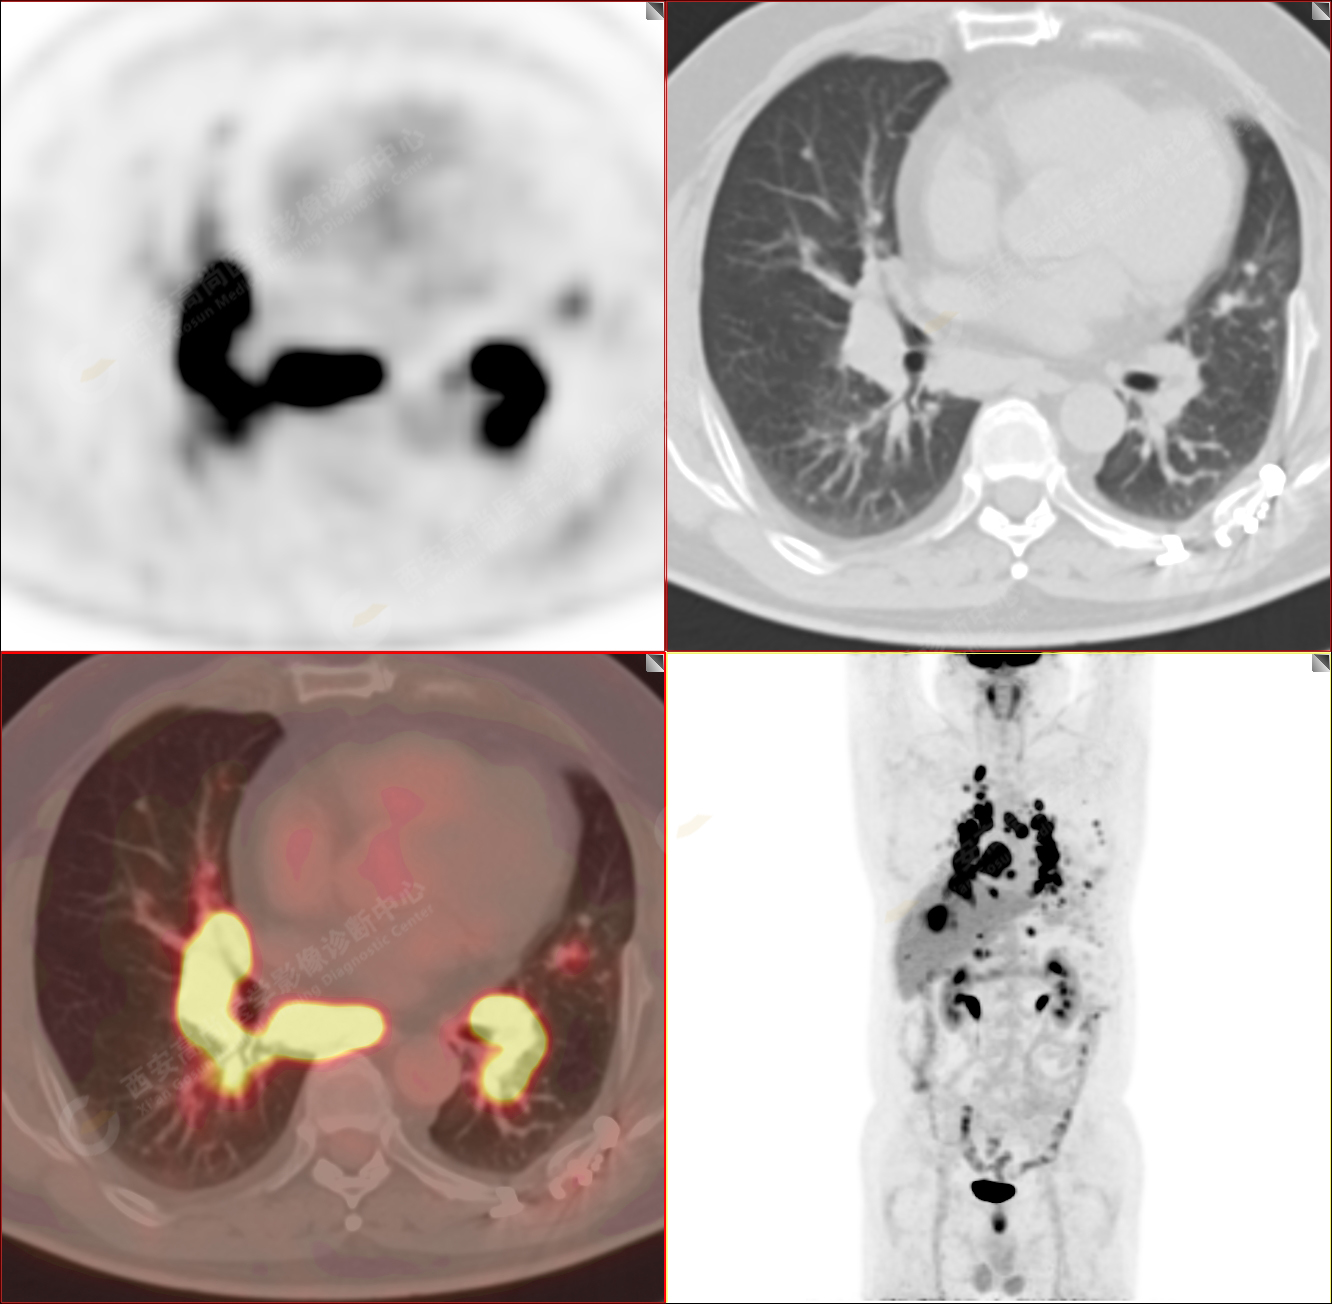

男性,53歲,頭暈半月入院,CT發(fā)現(xiàn)肺內(nèi)腫塊,雙肺多發(fā)大小不等實性及粟粒樣結(jié)節(jié),雙肺門及縱隔多發(fā)腫大淋巴結(jié)。病程中無發(fā)熱、胸悶氣及胸部不適。既往:左側(cè)肋骨外傷史。

PET/CT圖像